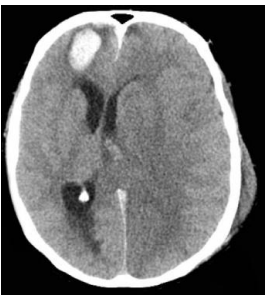

Atenção! O caso clínico a seguir refere-se à próxima questão.

Paciente de 19 anos, do sexo masculino, com relato de colisão

bicicleta x ônibus, com traumatismo cranioencefálico exclusivo,

com Glasgow 3 na cena e necessidade de intubação orotraqueal.

Deu entrada na sala de trauma, onde foi estabilizado e então

submetido a tomografia de corpo inteiro. Houve diversas

alterações apenas na tomografia de crânio – restante do exame de

imagem normal. Em seguida, levado ao centro cirúrgico, onde foi

submetido a passagem de dispositivo de monitorização de pressão

intracraniana (PIC) intraventricular. Após tal procedimento, foi

transferido à UTI. Dá entrada em mau estado geral, Glasgow 3T,

RASS -5 e com pupilas isomióticas, em uso de propofol 250mg/h,

fentanil 25mcg/h, intubado sob ventilação mecânica em

parâmetros baixos e sem drogas vasoativas.

Analise a tomografia de crânio a seguir.

A partir da análise da imagem acima, é correto afirmar que o escore de Marshall vale: